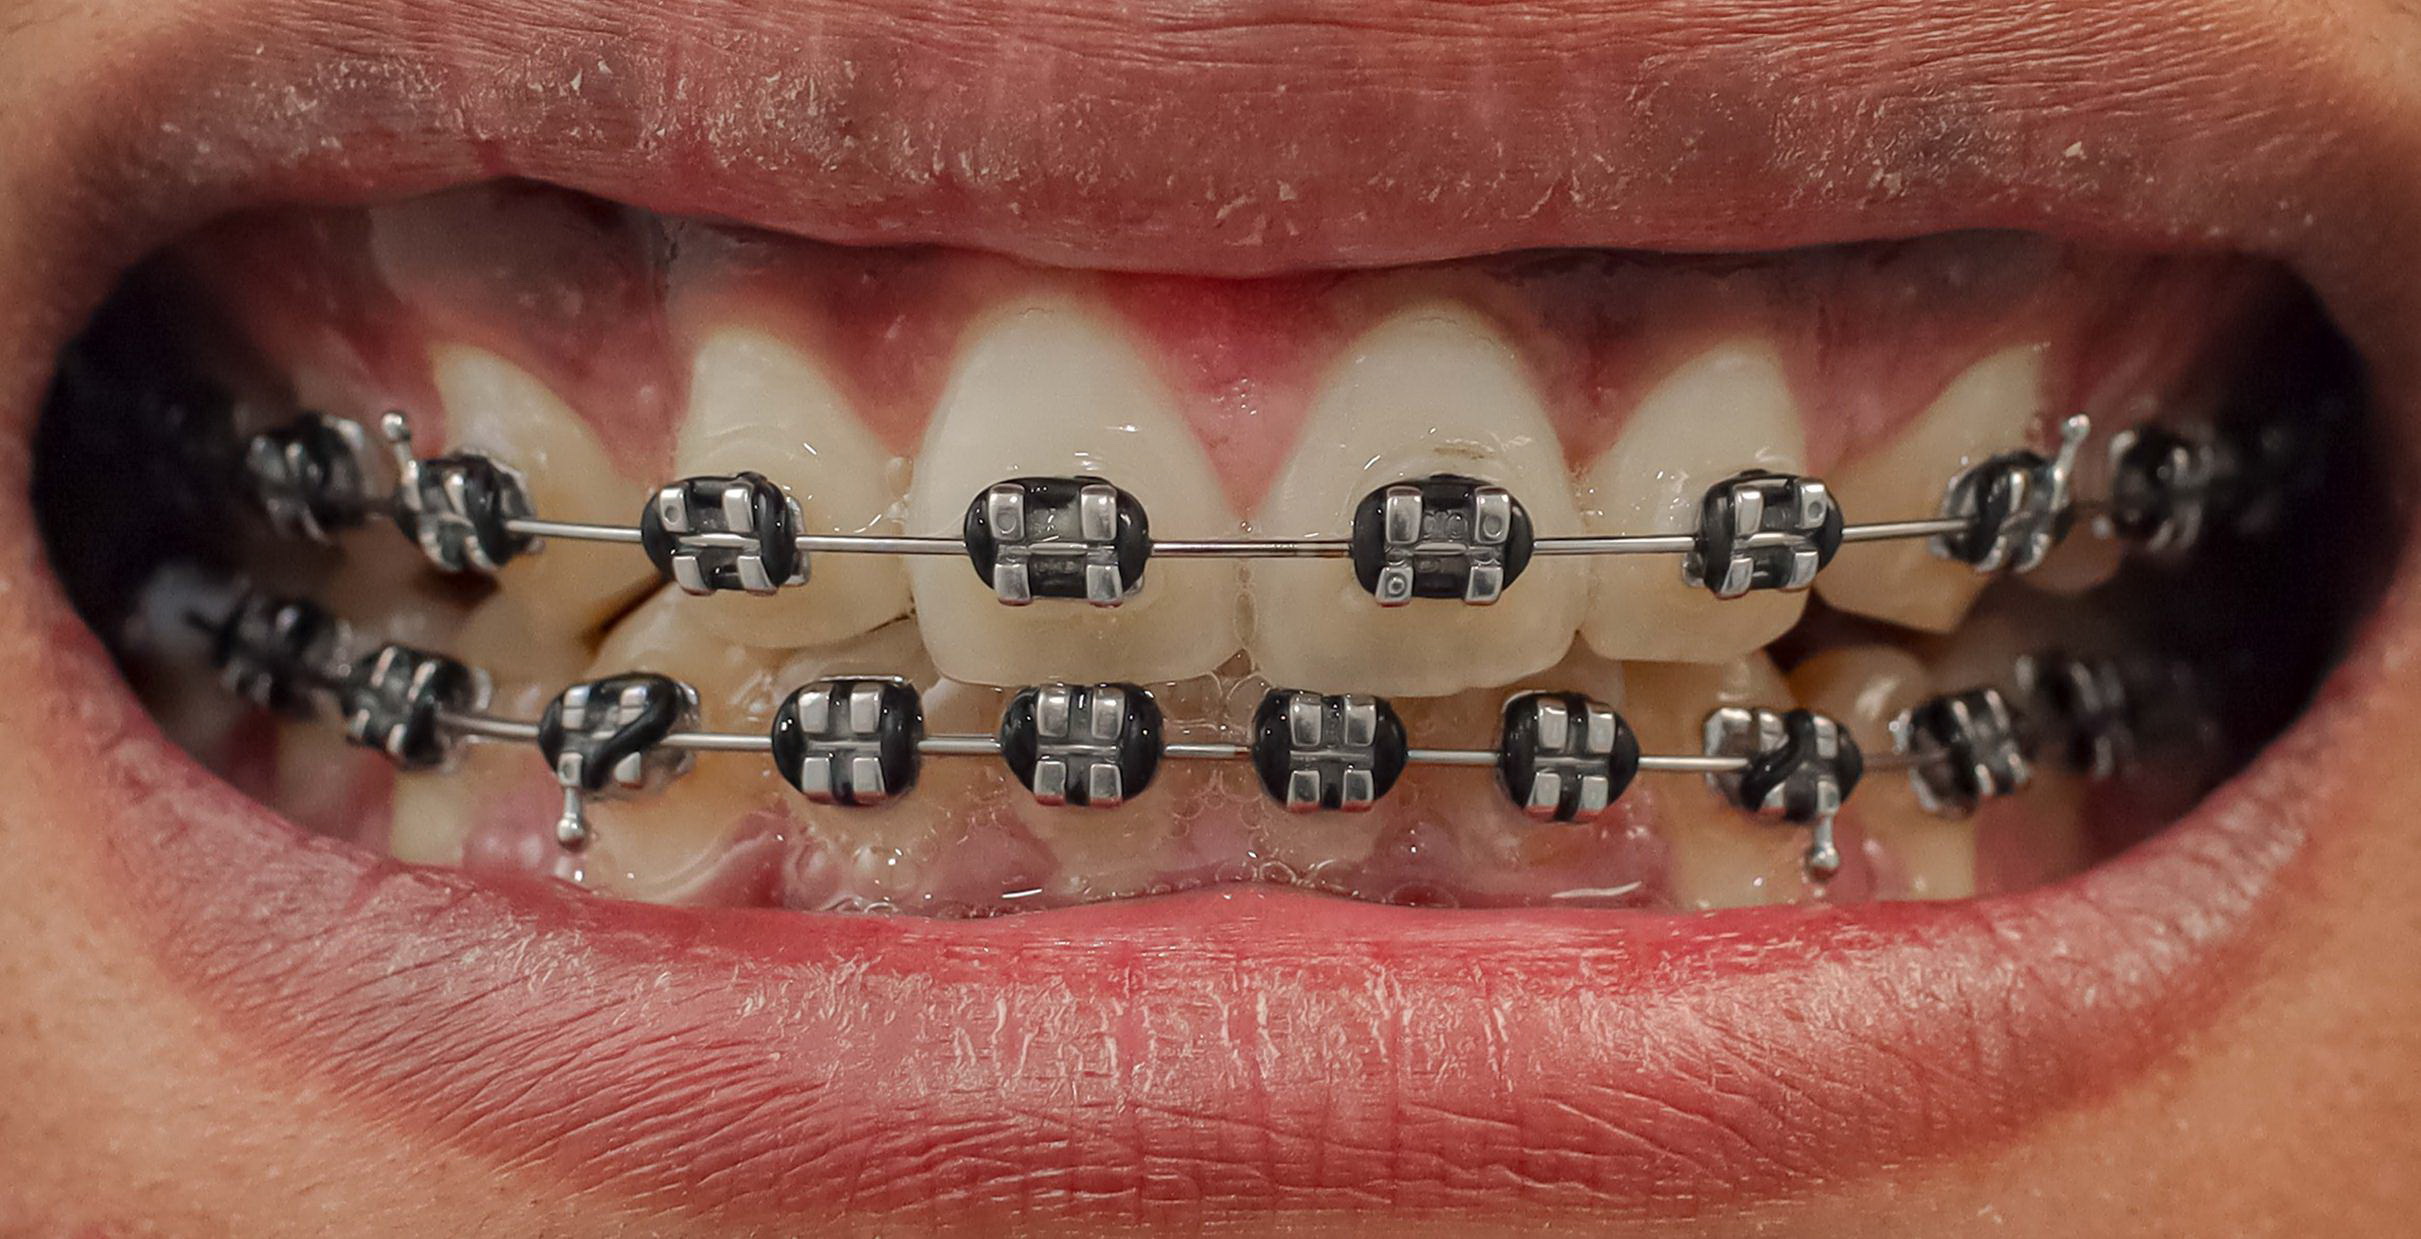

Traditional Braces & Fixed Appliances

Fixed orthodontic therapy requires precision and coordination.

You will learn about:

- Bracket systems and archwires

- Bonding procedures

- Instrument identification

- Adjustment appointments

- Debonding protocols

Understanding appliance mechanics helps you anticipate each step of the procedure and maintain smooth clinical flow.